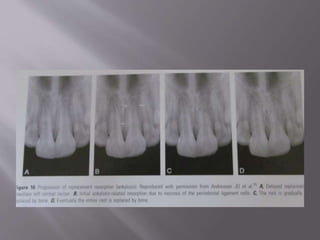

 Represents a sequel to a defect or injury to pdl cells, including the

cell layer next to the cementum.

Etiology

Acute trauma:- severe luxations

 Lateral luxations

 Intrusions

 Replantation of avulsed teeth

Homeostasis of pdl is lacking.

Healing events take place from adjacent healthy pdl or the bony

alveolus leading to formation of a normal pdl in former and a bony

bridge between socket wall and the root surface.